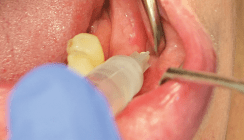

Für die prognostizierte Dauer des Eingriffs sollte die reduzierte Adrenalin­konzentration des 4%igen Articains 1:200.000 (Ultracain® DS, Sanofi-Aventis Deutschland GmbH) ausreichend sein (Abb. 3). Der Adrenalin­-gehalt ist zugleich hoch genug, um durch seine vasokonstriktorische Wirkung den Blutfluss im Injektionsgebiet zu reduzieren. Vor allem bei chirurgischen Eingriffen wird damit eine bes­-sere Übersicht am Eingriffsort erzielt (Abb. 4). Die Wirkdauer des Articains 1:200.000 ist ausreichend, um eine suffiziente postoperative Schmerzausschaltung zu erzielen. Die darüber hi­nausgehende postoperative Analgesie erfolgte bei Bedarf mit Ibuprofen 600.

Bei der in diesem Fall verwendeten In­filtrationsanästhesie erfolgte die Applikation von 1,7 ml Articain 1:200.000 am Nervus mentalis mit niedriger Geschwindigkeit von etwa 1 ml je 30 Se­kunden, um den Injektionsschmerz zu reduzieren. Die Weichteilanästhesie war auf Regio 31 bis 33 reduziert. Die Patientin gab postoperativ an, keine Schmerzen während der Behandlung gespürt zu haben. Nach Ausheilung der Gingiva um die Gingivaformer (Abb. 5) ist geplant, dass die Im­plantate prothetisch mit jeweils einer Suprakonstruktion versorgt werden und dazu – etwa 21 Tage später – die Abdrucknahme erfolgt.